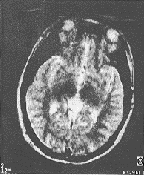

先天性松果体囊肿的MRI表现:①松果体四叠体池内圆形或类圆形囊性病灶,直径0.8~2.3 cm不等,周边有完整包膜。②囊性病灶信号均匀,T1WI显示囊壁为等信号,囊内容物为低信号,T2WI表现为均匀高信号。③注射Gd-DTPA之后,病灶囊壁轻度强化或不强化,内容物未见强化。④中脑导水管及第三脑室无扩大。⑤大脑大静脉流空效应存在(图1~4)。

图1 头颅轴位T1WI(TR/TE=500/30 ms)。松果体区见一低信号囊肿,壁薄、光滑

图2 头颅轴位T2WI(TR/TE=2800/90ms)。松果体区类圆形囊性病

灶呈均匀高信号,边缘光滑